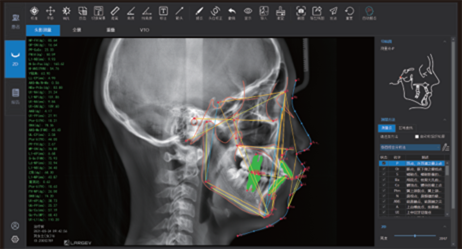

Finally, CEPH Measurement (Optional) in Dental CBCT (AI+CEPH)

The AI model analyzes large data sets to detect orthodontic landmarks and generate accurate cephalometric measurements and reports.

Therefore, orthodontists can assess and plan treatments with confidence.